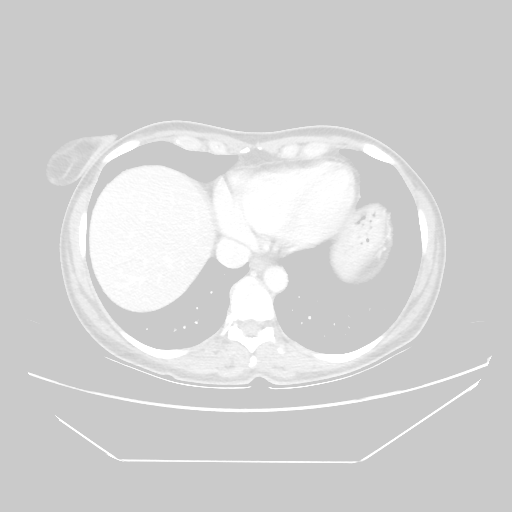

Reconstructed NATIVE CT scan (cycle consistency)

No window - Raw intensity values

Lung window (WL -600, WW 1500 β†’ Low βˆ’1350, High +150)

Mediastinum window (WL 40, WW 400 β†’ Low βˆ’160, High +240)